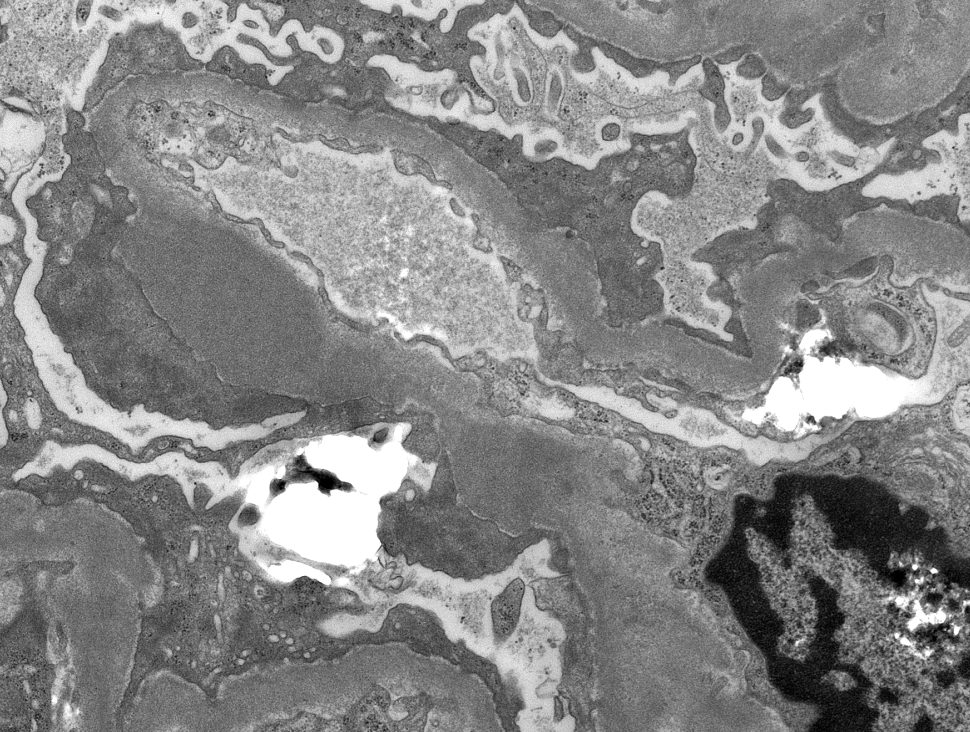

Mini case-series of crystal-storing histiocytosis (CSH) affecting predominantly glomerular loops with detailed literature review of renal CSH, images of one of the cases are depicted below, authors.elsevier.com/c/1Zh4S3uV~y8B…